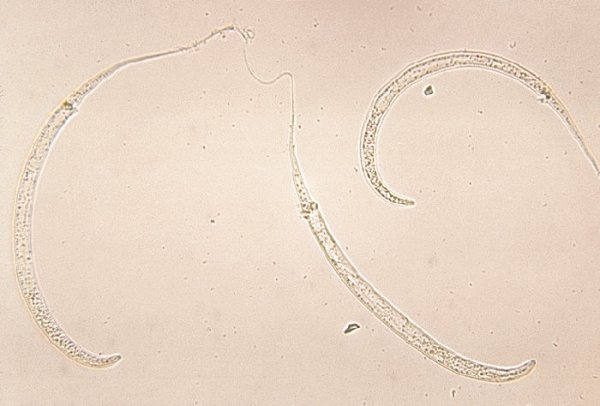

Loa loa — круглый червь, который паразитирует в подкожной жировой ткани человека и некоторых других приматов. Перемещаясь по тканям человеческого организма, он может добраться до глаз, поэтому получил неофициальное название «глазной червь».

В 2015 году был описан необычный случай. 25-летний пациент из Индии жаловался на боль в левом глазу. Выяснилось, что паразит попал в стекловидное тело — прозрачное вещество, заполняющее пространство между хрусталиком и сетчаткой в глазу.

Медики описали его как «довольно длинного червя, который двигался беспорядочно и бесцеремонно». Паразита удалили в ходе хирургической операции. Вмешательство прошло успешно: через две недели боли прошли, а зрение значительно улучшилось.